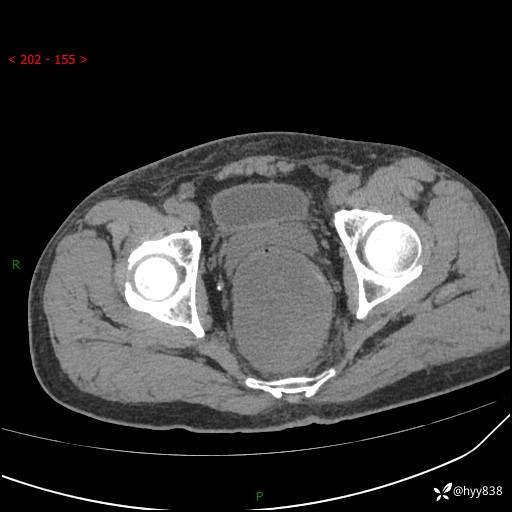

盆腔CT平扫+增强